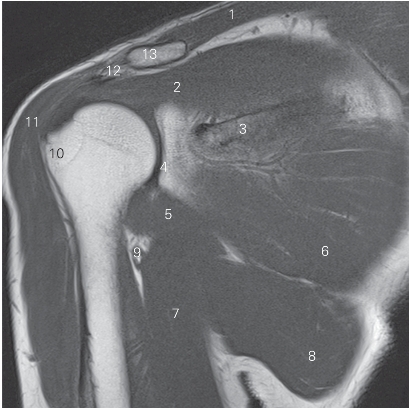

图4-19 经肩峰的矢状断层MR T2WI FS

1 冈上肌 supraspinatus 2 肩峰 acromion

3 冈下肌 infraspinatus 4 肱骨头 head of humerus

5 肱骨大结节 greater tubercle 6 小圆肌 teres minor

7 三角肌 deltoid 8 肱三头肌 triceps brachii

9 肱二头肌 biceps brachii 10 胸大肌 pectoralis major

11 肱骨小结节 lesser tubercle 12 肩胛下肌 subscapularis

图4-20 经肱二头肌短头的矢状断层MR T2WI FS